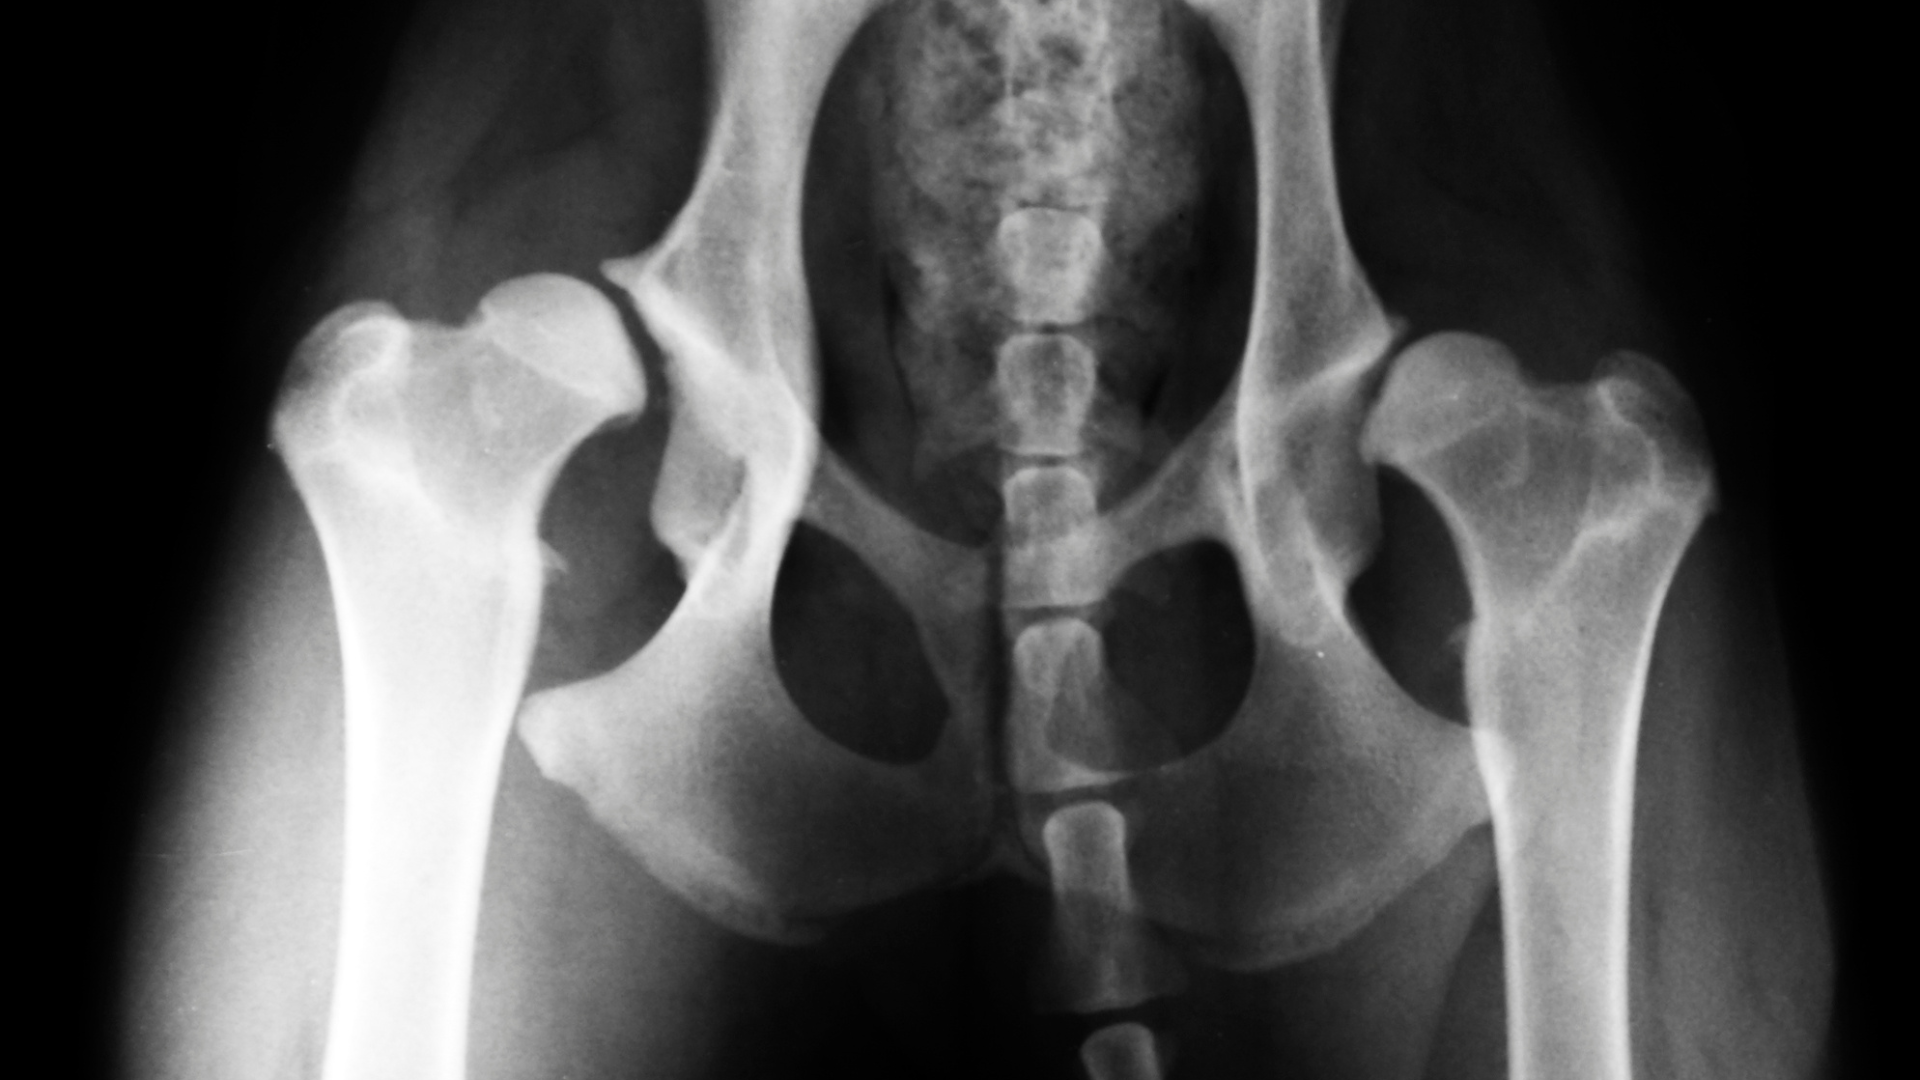

For spinal tumors, some dogs will show neurological symptoms like seizures or changes in behavior. About 75-85% of osteosarcoma cases are associated with limbs. However, tumors can also develop in the jaw, spine, ribs, and pelvis. In addition to location-specific signs, dogs often exhibit signs of fatigue and a lack of interest in daily activities, such as walks or playing.

X-rays are needed to provide a diagnosis for bone cancer. If your vet detects abnormalities on the X-rays, they may also recommend a bone biopsy to check for cancerous cells. Once a diagnosis is made, several treatment options may be considered. Amputation of the limb is a standard option and can prevent the spread of cancer.